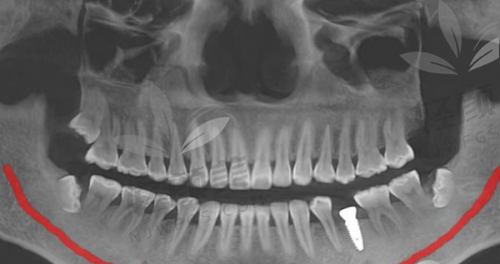

有人说,种植牙这项目,是牙科界的“豪车”——价格高、操作精、材料贵。但在贝壳口腔,种牙也能走“性价比路线”。以下是根据法定数据和实地探访,整理出的2026价目明细:

种植牙价目表(单颗)

▪ 韩国登腾:3988元起

▪ 韩国奥齿泰:4680元起

▪ 美国皓圣:5280元起

▪ 瑞士ITI:6980元起

▪ 德国费亚丹:8680元起

▪ 瑞典诺贝尔:9500元起

划重点:以上价格包括牙冠+种植体+基台,有些医院会偷偷只标“种植体价格”,结果“牙冠另收3800,基台另算1500”,到账单才发现多花了5000块。还没唤醒医疗保险,钱包已经睡着……贝壳口腔各分院在面诊当天会打印详细账单列表,让费用变得“看得见,摸得着”!